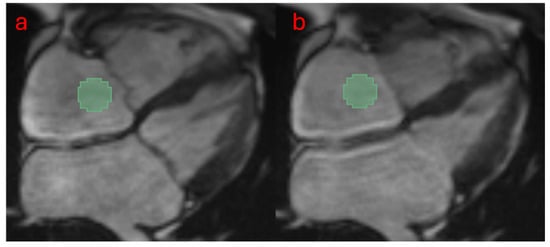

2.6. Radiomic Feature Extraction at Ventricular Systole